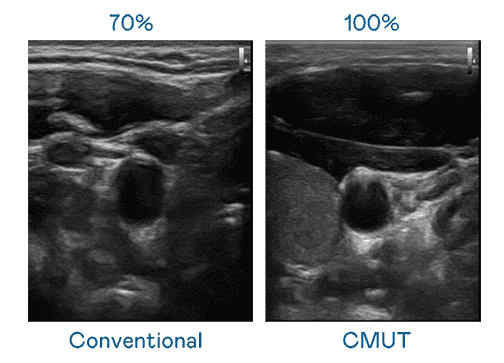

CMUT 技术是一种用电容式微机电元件来产生超音波讯号的技术。。与传统 PZT 压电式技术相比,,,CMUT 频宽增加 30%,,更宽频的超音波讯号让影像解析度大幅提升,,,是实现高影像品质医疗超音波扫描、、促进精准医疗发展的关键技术。。。。

大频宽带来超清晰影像

超音波影像的解析度高低,,首先取决于探头能发出的讯号频宽。。。赏金国际 CMUT 可提供高清晰的超音波讯号,,,,提供高频宽、、高灵敏度、、、、影像纹理细节更高的超音波影像,,,协助医护人员缩短影像判读时间及利用精准的医疗影像进行诊断。。